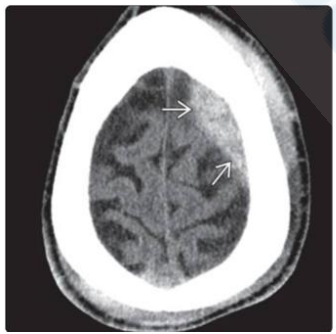

No traumatismo cranioencefálico, a correta identificação das lesões estruturais é de suma importância para determinar o tratamento a ser empregado. Considerando esse fator, analise a Figura 2 abaixo:

Figura 2

Considerando um desvio da linha média de 6 mm e sem lesões >25 mL, assinale a alternativa correta sobre a classificação de Marshall apresentada no exame e sua definição.